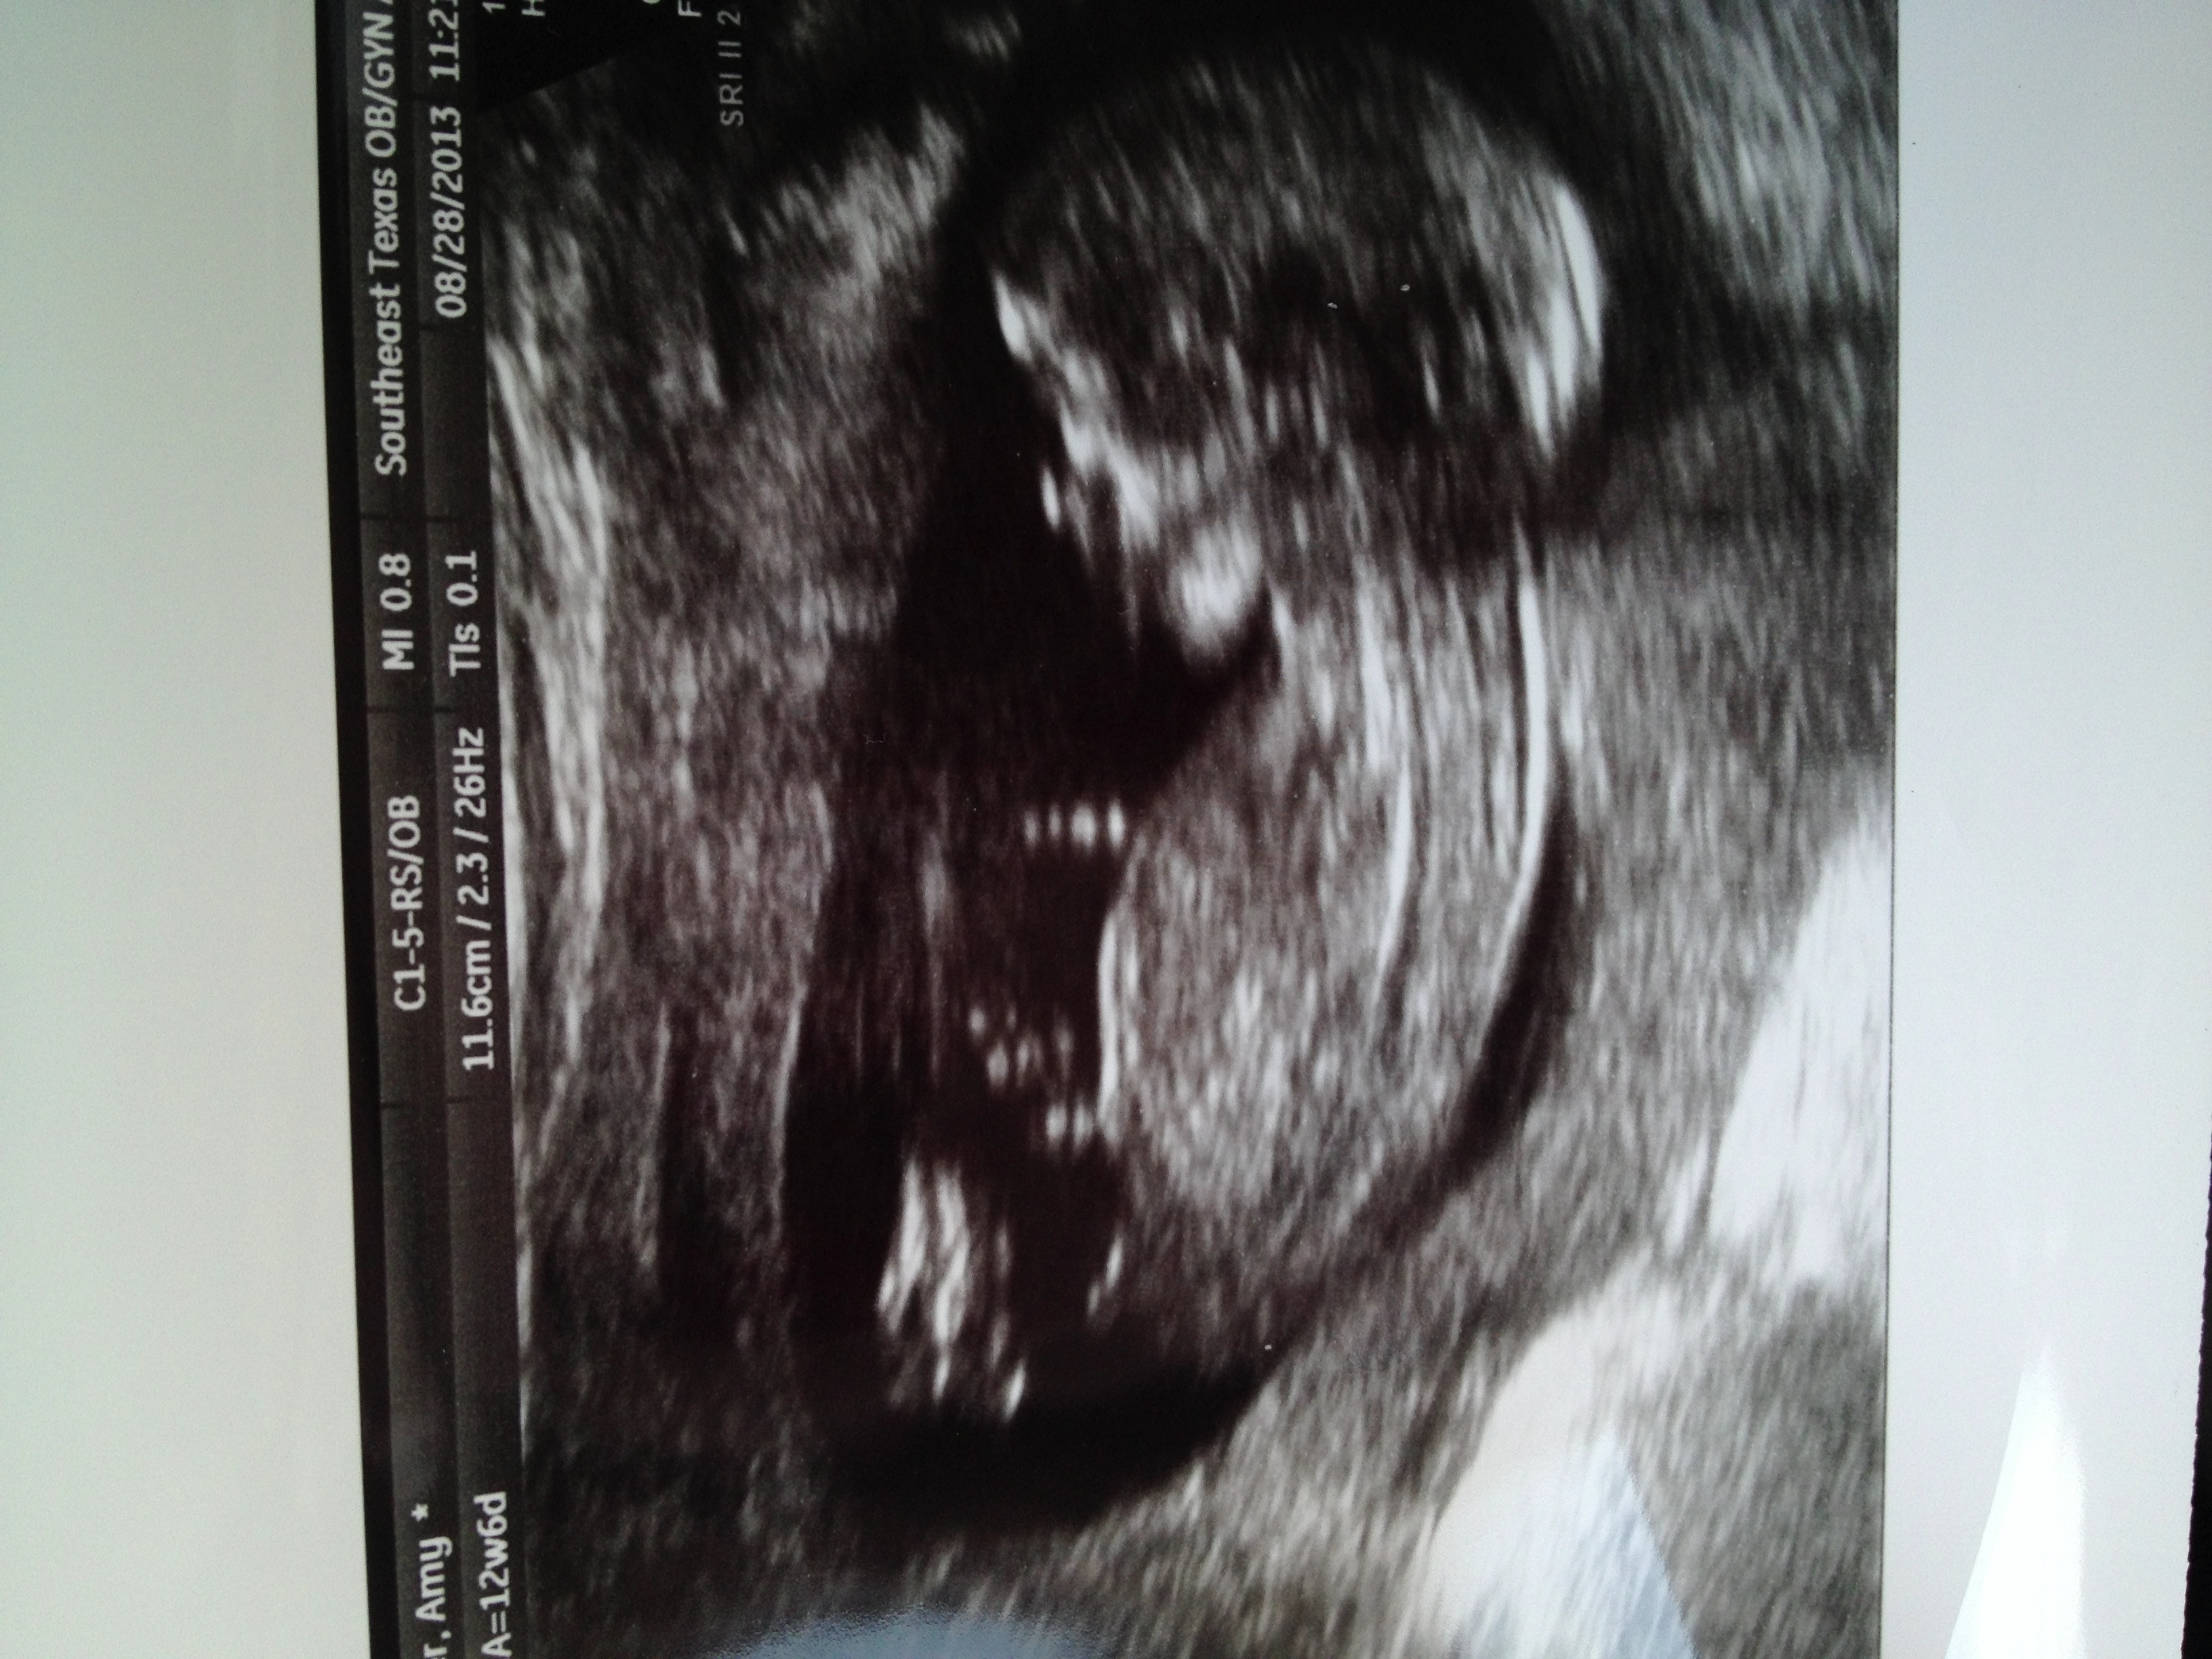

Started spotting last night so my doc wanted to do an ultrasound so see what was going on! Have a SCH and is now on pelvic rest. But i got to see my baby! They couldnt tell the sex yet..but everyone is saying boy. Anyone want to take a guess?!